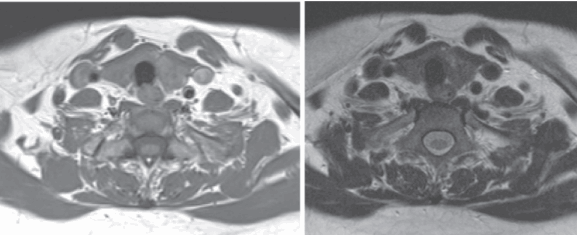

(Слева) На аксиальном рисунке изображена язычная щитовидная железа в задних отделах языка по средней линии, непосредственно глубже слепого отверстия. Четкие контуры и срединное расположение в области дна полости рта или в основании языка - типичные признаки язычной щитовидной железы.

(Справа) На аксиальной КТ с КУ в основании языка по средней линии определяется округлое контрастирующееся образование с четкими контурами, с минимальной деформацией подбородочно-язычных мышц. Плотность язычной щитовидной железы намного выше по сравнению с минимально контрастирующейся язычной миндалиной.

(Слева) На аксиальной КТ с КУ в области дна по средней линии определяется объемное образование с четкими контурами, представленное эктопической тканью щитовидной железы неоднородной плотности (может быть сопоставимо с ранними изменениями при зобе).

(Справа) На сагиттальной MPT (STIR, срединный срез) в основании языка визуализируется объемное образование с неоднородным гиперинтенсивным сигналом, заполняющее валлекулу. В этом случае язычная щитовидная железа обусловливает значительное сужение просвета ротоглотки, смещая надгортанник кзади и книзу.